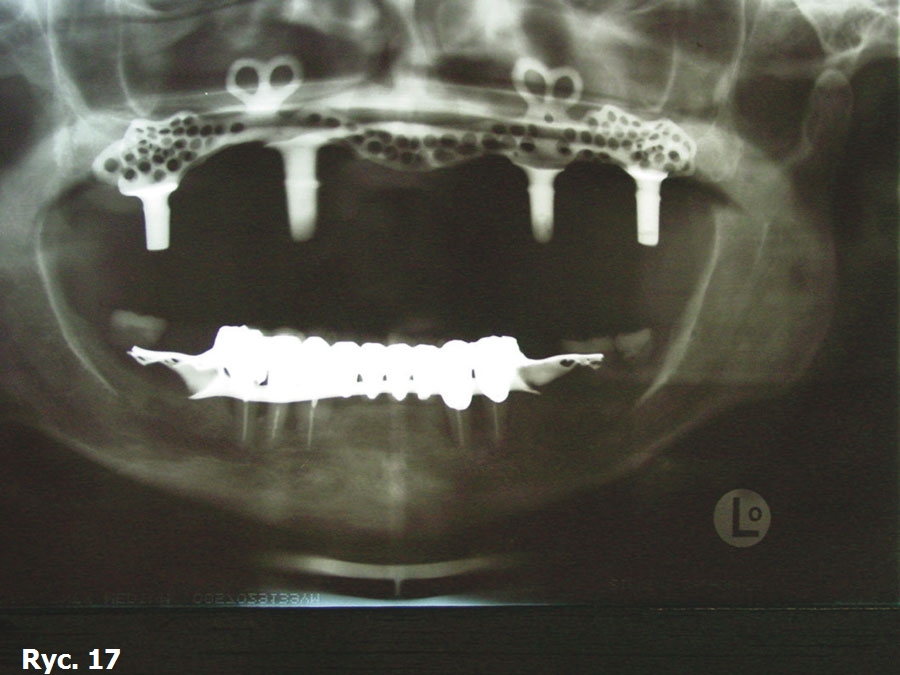

Obrazy TK oraz modele stereolitograficzne ukazują wysoki stopień zaniku tkanek twardych szczęki. Z tego powodu wykonano projekt wszczepu podokostnowego full arch (ryc. 14), który odlano z 5. gatunku tytanu (ryc. 15) i wszczepiono. Zabieg odbył się bez powikłań (ryc. 16). Leczenie zakończyło się wykonaniem i oddaniem protezy stałej full arch typu all on four, która w pełni zaspokaja estetyczne oraz funcjonalne oczekiwania pacjentki (ryc. 17, 18, 19, 20, 21).

Wszczepy podokostnowe - przypadek 3 (ryciny)